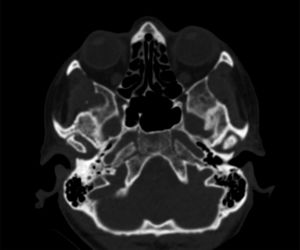

Presentamos el caso de una paciente de 72 años diagnosticada de una variante de EOP monostótica (afectación de cúbito) de 5 años de evolución, en tratamiento en primera instancia con analgésicos (AINE, paracetamol, inhibidores de la COX-2) y posteriormente con alendronato vía oral a dosis de 40mg trimestrales junto con suplementos de vitamina D (400U) y Ca (1,5g). La paciente fue remitida a nuestro servicio por presentar dolor (VAS=7/10) en la articulación temporomandibular (ATM) derecha y disminución de la apertura oral (<2,5cm). El estudio se completó mediante la realización de tomografía axial computarizada (TAC), en la que se apreció deformidad condilar con osteoesclerosis y osteofitos (fig. 1). Diagnosticada como artropatía de ATM fue tratada en primera instancia mediante férula de descarga maxilar, ejercicios de rehabilitación, tratamiento analgésico y relajantes musculares. Tras revisiones periódicas trimestrales, al año de tratamiento se apreció reducción del dolor (VAS: 3/10) y aumento de la funcionalidad articular con apertura oral superior a 3cm.